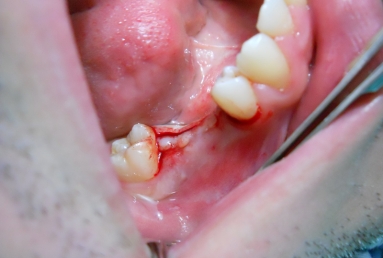

Initial situation: two missing teeth, second lower premolar and first lower molar. two dental implant are integrating in the mandibular bone for 4 months, then, gingival healing caps are applied for 3 weeks. an impression is taken for the dental lab in order to manufacture 2 porcelain fused to metal crowns. they will be screwed directly in the implant body.